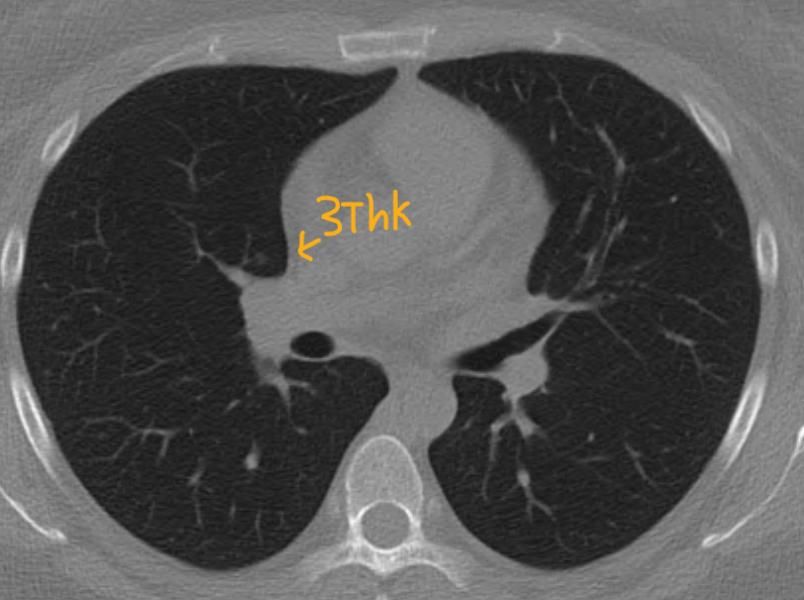

*좀더 하얀색인 사진 2장은 24년 조영제 폐CT 이고, 나머지 3장은 25년 저선량 CT사진입니다.

♧ 고형 같나요 간유리 같나요?

Ai 는 우상엽 solid라는데 오늘 2차병원에서 중간위치고 간유리에 가깝다라고 들어서요

solid nodule인지 ground glass nodule인지는 clear cut하게 나누어지는 것이 아닙니다. 결절이 색이 또렷하면 solid nodule인 것이고 흐지부지하면 ground glass nodule인 것입니다. 이건 육안 소견을 두고 말하는 것입니다. 따라서 일부 nodule에 있어서는 판독하는 의사에 따라 소견이 다를 수 있습니다.